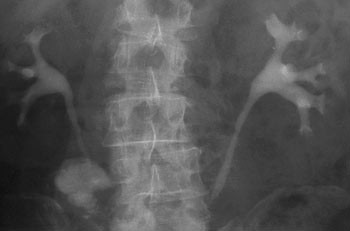

Begrunnelsen for å følge opp pasientene med røntgenurografi de første månedene etter operasjonen er å påvise passasjehinder som kan skade nyrene (fig 1 – 3). Vi fant lett utvidelse hos over halvparten av pasientene som ble undersøkt innen seks måneder etter operasjon. Dette er i samsvar med en studie av Thoeny og medarbeidere, der utvidelse forekom i 80 % av tilfellene. I deres studie var imidlertid alle grader av utvidelse tatt med og kun pasienter med ortotopisk blæresubstitutt var inkludert, mens vi tok med pasienter med ulike typer urinavledning.